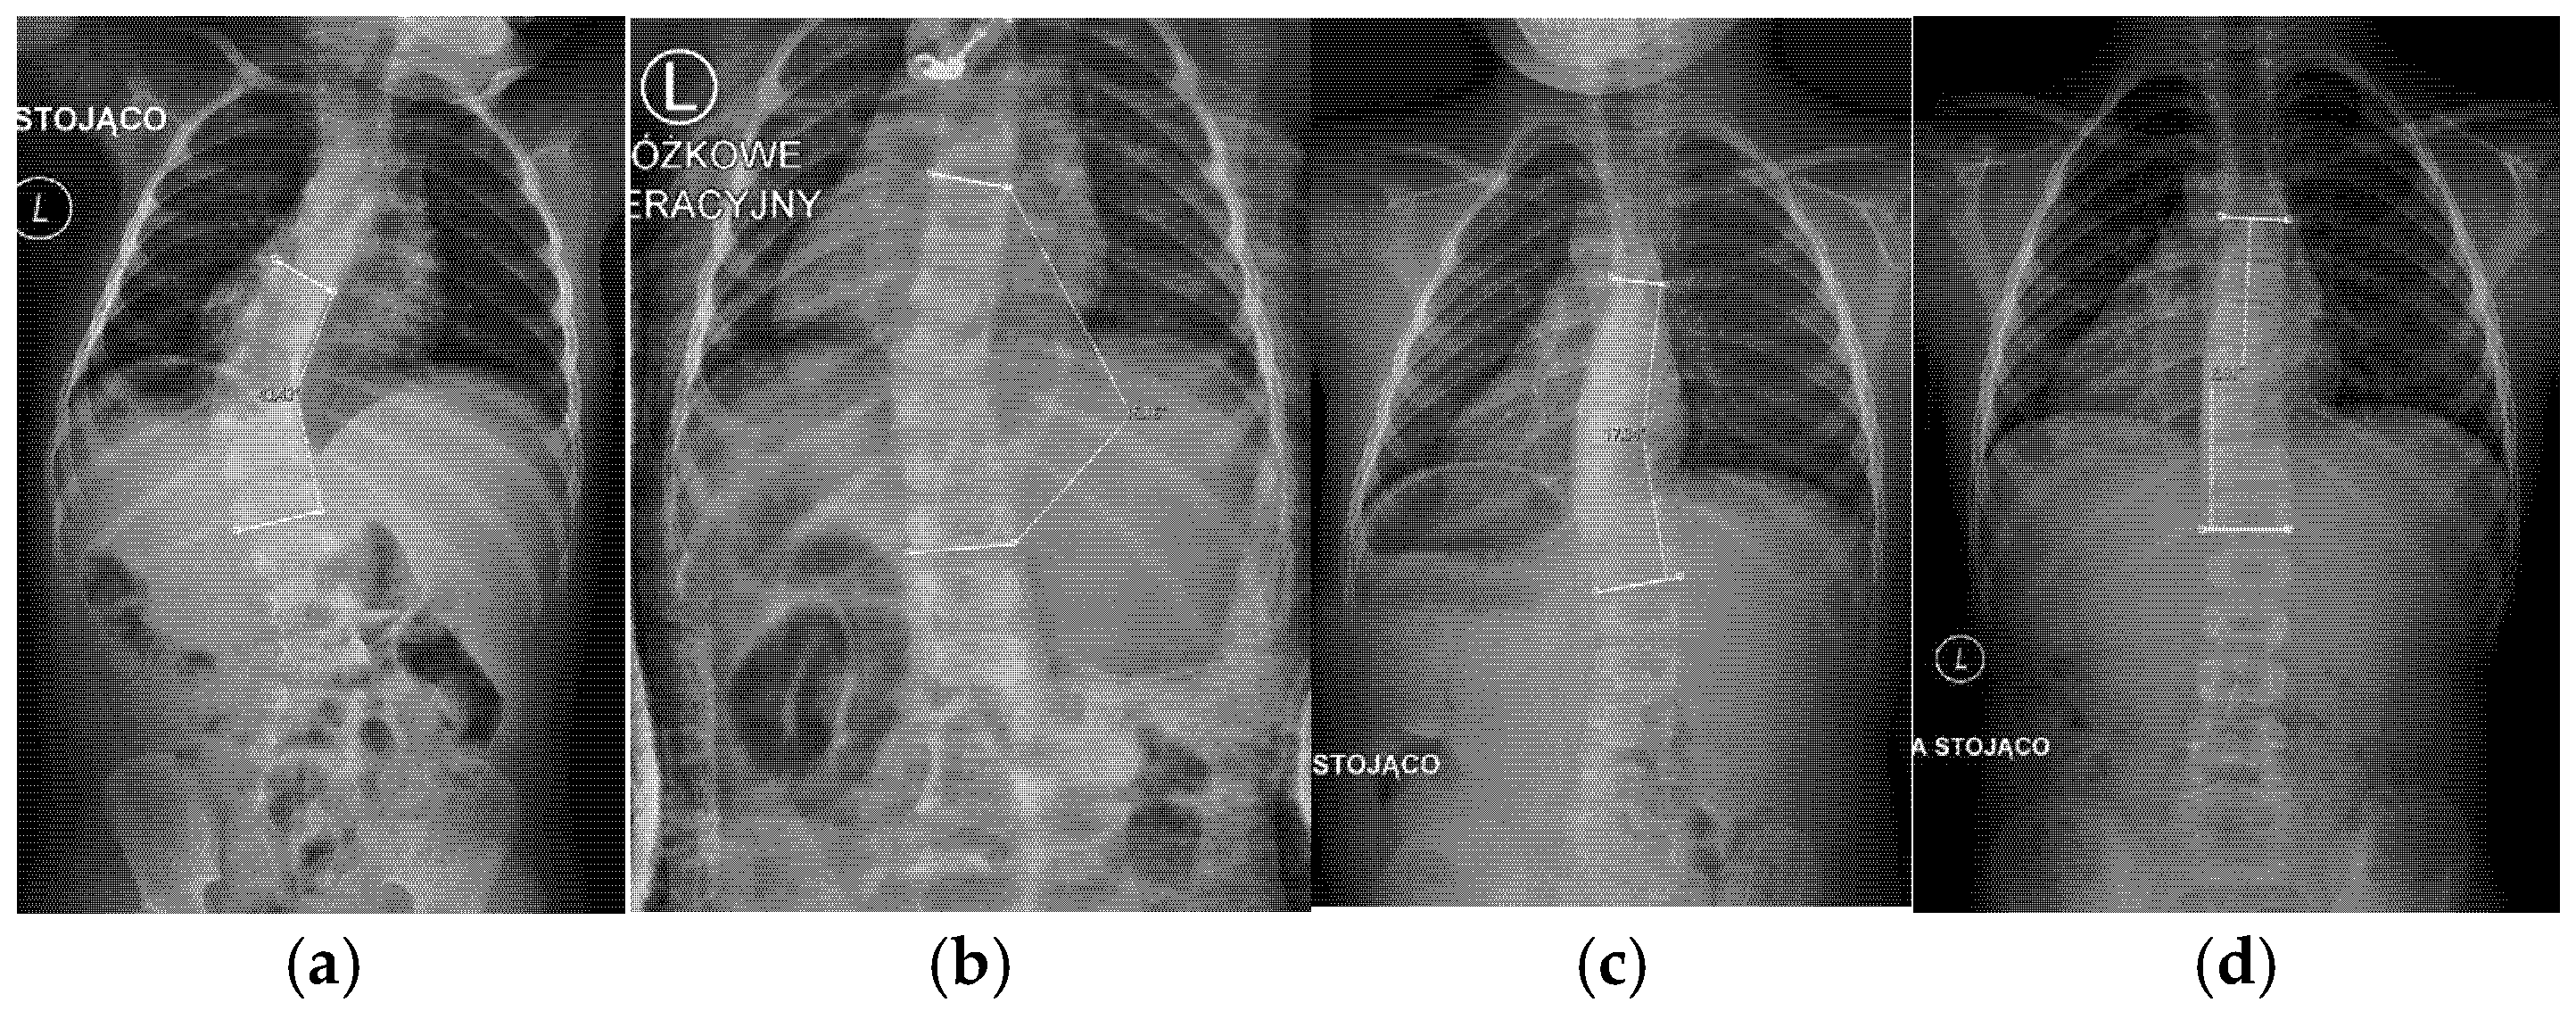

The final cohort of 15 children with EOS was analyzed. The mean age at the beginning of Mehta casting was 2.14 years (Figure 5). Each patient underwent, on average, 5.0 serial casts, with a mean casting interval of 10.9 weeks.

Figure 5.

Patient GM, with early onset scoliosis: (a) before treatment, age 1.5 years, Cobb angle 43°; (b) during casting, age 2 years; (c) after treatment, age 4.1, Cobb angle 17°; (d) follow up, age 7.11 years, Cobb angle 3°.